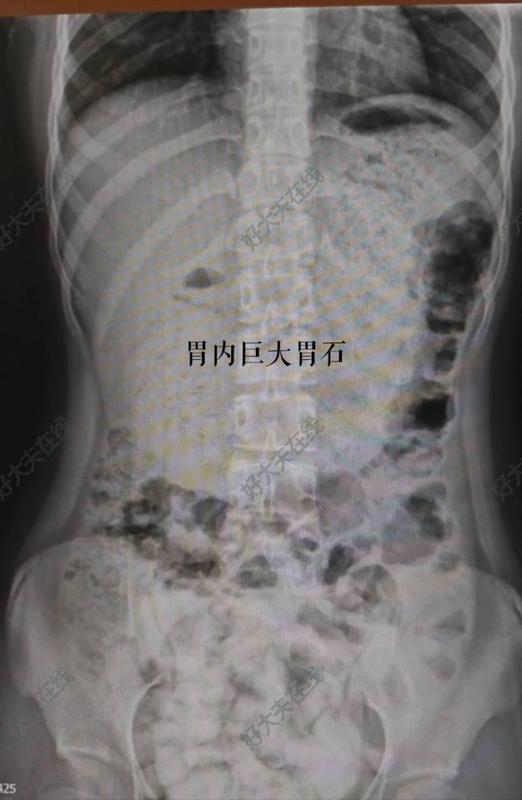

治療前14歲女孩,既往1年前曾因進(jìn)食大量頭發(fā)形成胃石,于我科予口服碳酸飲料后自行排出。此次因腹痛再次入院,CT提示胃內(nèi)巨大胃石,為再次進(jìn)食大量頭發(fā)所致。予口服碳酸飲料、胃鏡等均無法排出。遂擬行手術(shù)治療。為使得女孩術(shù)后腹部瘢痕隱匿,并減小創(chuàng)傷,遂選擇單孔腹腔鏡手術(shù)。治療中術(shù)中經(jīng)臍單孔腹腔鏡提出胃前壁,取出約1斤頭發(fā)治療后治療后即刻術(shù)后一周出院,腹部幾無瘢痕,患兒及其家屬較為滿意。